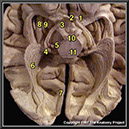

N1A6P4

24